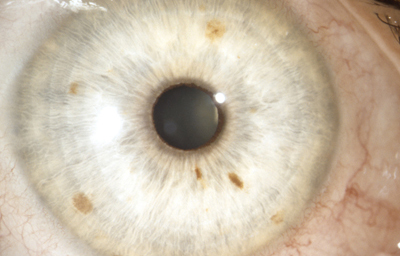

El Color del Iris

El Iris en general es muy pigmentado con colores que comúnmente van del marrón, avellana, gris, verde y azul. Existen los iris sin pigmento en el Albinismo oculo-cutáneo en cuyo caso se ven blanco/rosados.

El color del Iris es un fenómeno complejo por efectos combinados por la textura, la pigmentación y el tejido fibrovascular del estroma, junto con la constitución epigenética del individuo. Desde el punto de vista óptico, la simple absorción o reflexión selectiva por algunas moléculas, como la hemoglobina o el colágeno del estroma que son componentes no pigmentados, puede tener influencia en el color que es observado.

A pesar de la gran variedad en el color del Iris, el único pigmento que contribuye en forma sustancial es la melanina; su cantidad, es uno de los factores que determina el color del iris en una persona. Estructuralmente el color depende de la cantidad variable de eumelanina (melaninas marron/negra) y pheomelanina (melaninas rojo/amarillo) producidas por los melanocitos derivados de la Cresta Neural. El grado de dispersión de la melanina que yace en racimos subcelulares en los melanosomas, tiene cierta influencia en el color que se observa, pero el grado de dispersión no es reversible ya que los melanosomas no son moviles.